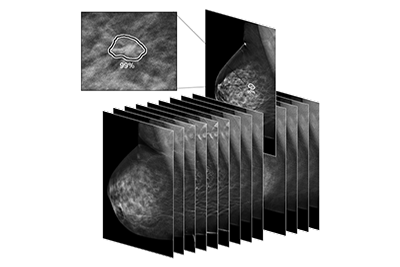

May 16, 2022 — iCAD, Inc., a global medical technology leader providing innovative cancer detection and therapy solutions, today announced that promising clinical research supporting ProFound AI® Risk for Digital Breast Tomosynthesis (DBT) – the world’s first clinical decision support tool that provides an accurate short-term breast cancer risk estimation based on age, breast density and mammographic features – was recently published in the peer-reviewed journal, Science Translational Medicine.[iv]

In the study, which involved 154,200 women screened at four participating U.S. screening sites[v] using DBT from 2014-2019, researchers at the Karolinska Institutet in Stockholm, Sweden found ProFound AI Risk accurately determined women who were at a higher risk of developing breast cancer, with an area under the receiver operating characteristics curve (AUC) of 0.82iv, (95% CI 0.79-0.85). AUC is a standard performance measurement for examination procedures that incorporates sensitivity and specificity into a single metric of overall performance. This data supports iCAD’s internal research, which previously found ProFound AI Risk for DBT offers an AUC of 0.80 (95% CI 0.76, 0.83).[vi]

Established lifestyle-familial risk models, such as Tyrer-Cuzick and Gail, are currently used in the U.S. to identify women with a greater than 20% lifetime risk of developing breast cancer who could be offered breast magnetic resonance imaging (MRI) as a supplemental screening modality for breast cancer detection.iv However, these long-term risk models can result in a high number of false positives due to low-to-moderate discrimination performance.[ix] ProFound AI Risk complements traditional risk models and is easy for clinicians and medical facilities to adopt, as it only requires the images from a 2D or 3D mammogram, with no questionnaires, portals, or staff required to implement.